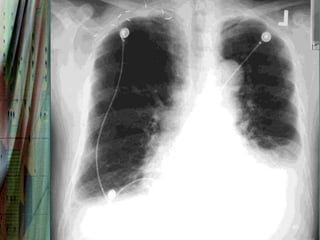

Radiography

Chest radiography is helpful in distinguishing CPE from other

pulmonary causes of severe dyspnea.

Features that suggest CPE rather than NCPE and other lung

pathologies include the following:

•   Enlarged heart

•   Inverted blood flow

•   Kerley lines

•   Basilar edema (vs diffuse edema)

•   Absence of air bronchograms

•   Presence of pleural effusion (particularly bilateral and

36

symmetrical pleural effusions)

37

38